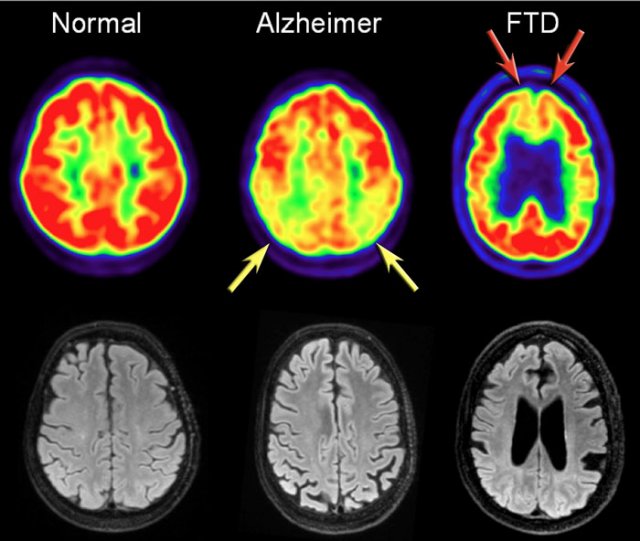

dementia mri frontotemporal radiopaedia sagittal brain version original size full t1

mri memory loss brain dementia ucla scans alzhiemers tbi study

dementia lobe atrophy frontal degeneration types vascular frontotemporal temporal cortical tissue overview

dementia mri diagnosis brain scan temporal step first patient healthcare europe variant lobar degeneration affects lobes semantic predominantly frontotemporal